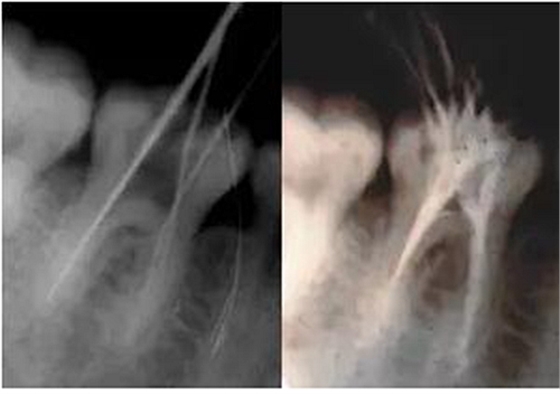

3、根管口的直線通道:特別對于彎曲根管!預備根管之前是否重視這個環(huán)節(jié),盡管找到了根管口,銼也能順利進入根管,但根管口的直線通道是否建立也是衡量醫(yī)生操作技能的重要依據(jù)。

方法很多:手動器械操作時我們可以采用價格便宜的“GG”鉆,PROTAPER機動預備時可以采用SX銼。

圖7彎曲根管冠部處理之前 圖8用GG鉆或SX銼進行預備

圖9處理后形成的直線通道

我的病例1_冠部處理成直線通道后的充填效果

我的病例2_下頜7"C"型根管的充填效果